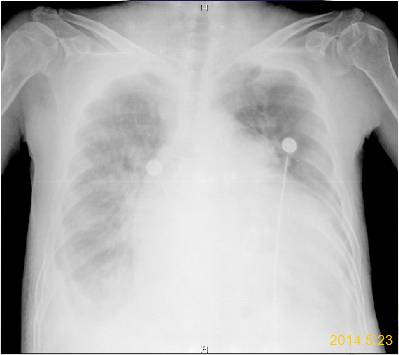

6. 5.23

急诊床旁胸片:两肺淤血,双肺透过度减低;主动脉结不宽;肺动脉段凸出;全心大;心影内可见人工瓣环影;胸骨可见固定钢丝影;双侧肋膈角模糊。

印象:术后改变,心功能不全,肺水肿,双侧胸腔积液。